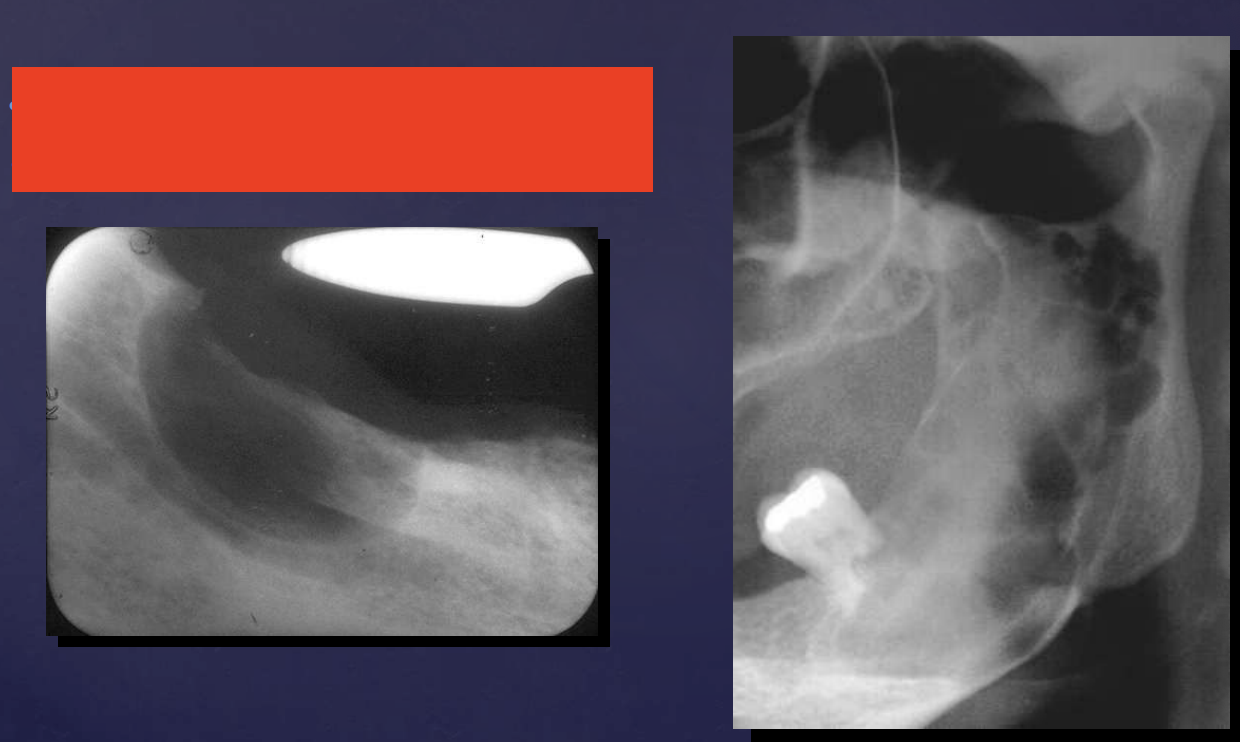

radiographically, Unicystic Ameloblastomas often mimic what?

dentigerous cysts

Unicystic Ameloblastomas

expansion/thinng ext. oblique ridge